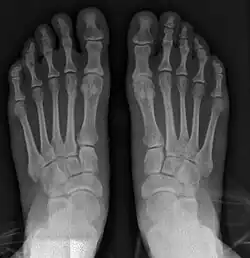

Bunion (hallux valgus) deformity is actually part of a complex of anatomical derangements of protruding mass (bunion), buckling of big toe (hallux valgus) and the bone behind it (metatarsus primus varus), displaced sesamoid bones (detrimental to the important walking function of big toe), collapsed metatarsal arch and several other secondary changes that are the domino effects of metatarsal primus varus. Thus, metatarsus primus varus correction has become the primary objective of all bunion surgeries.

Primus varus deformity

Primus varus deformity is the leaning of the first metatarsal bone away from the second metatarsal and towards the opposite foot (Fig. 1). As it leans over, its head sticks out to form the bunion bump and it also widens the forefoot to cause shoes feeling too tight. Thus when bunion pain becomes unmanageable, surgical correction is to narrow the forefoot by repositioning of the first metatarsal head back to its normal position. This can be done by osteotomy (bone-breaking), soft tissue (non-osteotomy) or fusion techniques.